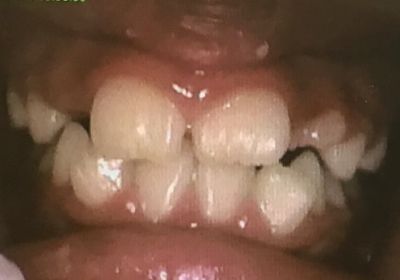

実際の症例

- 症例1

-

2019.12.3

2020.3.15

2020.7.29

2024.7.16

- 症例1(トレーニング)

MFT初回

MFT開始から5年後